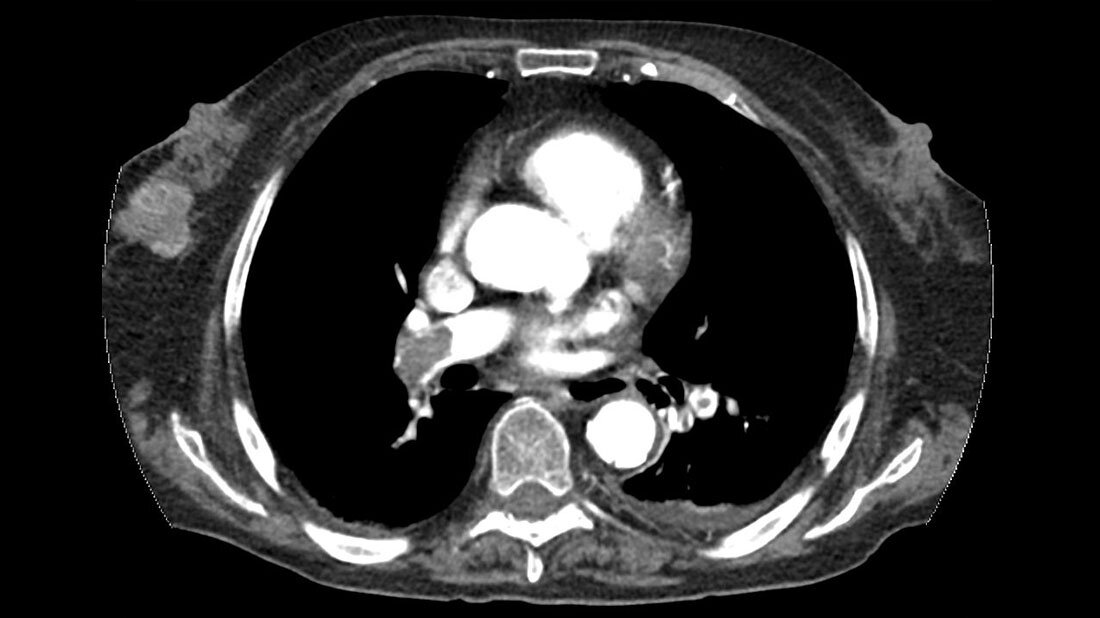

In der konventionellen Radiologie gehört der Thorax zu den am häufigsten untersuchten Regionen. Durch die Fortschritte bei Computertomografie und Magnetresonanztomografie konnte die Auflösung erheblich gesteigert werden. Das erhöht die Früherkennung von Krankheiten. Dabei ist es wichtig, immer auch ein Auge auf die mitabgebildeten Organe und Strukturen zu werfen. Eine Umgebungsdiagnostik ist bei der Anfertigung der CT-Bilder enorm wichtig. Je häufiger sich eine MTR am Gerät die angefertigten Bilder auch anschaut, desto schneller kann man auf eventuelle Zufallsbefunde reagieren und gegebenenfalls das Untersuchungsmanagement anpassen. Einige Fallbeispiele werden im Beitrag vorgestellt.

The thorax is one of the most frequently examined regions in conventional radiology. Thanks to advances in computed tomography and magnetic resonance imaging, the resolution has increased significantly. This increases the early detection of diseases. It is important to always keep an eye on the organs and structures that are also shown. Surrounding diagnostics are extremely important when preparing the CT images. The more often an MTR/radiographer looks at the images produced on the device, the faster one can react to any incidental findings and, if necessary, adapt the examination management. Some case studies are presented in the article.